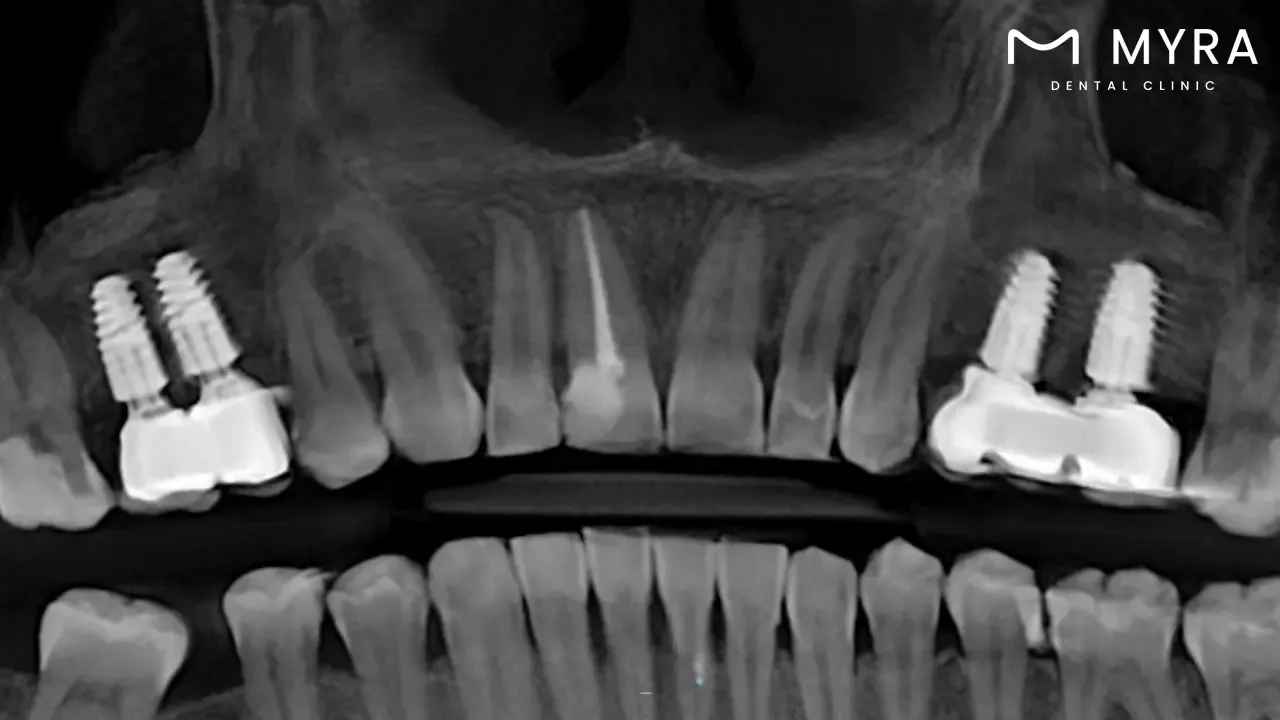

2. Dental implants

Dental implants are artificial tooth roots that are inserted into the jawbone via a surgical procedure. They are used to replace one or more lost teeth. These implants, which are mostly made of titanium, a material that is biocompatible, and are put into the jawbone in such a way as to duplicate the root structure of a tooth, are generally biocompatible.

Osseointegration is the process by which the bone grows around the implant and integrates with it; it happens over the course of time and keeps the implant firmly in place. The top of the implant is fitted with an abutment after the fusion has taken place, which makes it achievable to restore the missing tooth with a dental crown, bridge, or denture. The end result is a tooth replacement that appears and functions just like a natural tooth.

Dental implants are becoming increasingly popular as a result of their long-term durability and stability as well as their nearly natural feel and function. They not only provide a replacement that is aesthetically beautiful, but they help in protecting the bone structure, which frequently deteriorates when a tooth is lost. Bone health, oral cleanliness, and overall health all have an effect on the success and longevity of dental implants, so it's important to get a professional opinion before making the decision to get implants.

Dental implants are one of the most expensive treatments that are performed in the dentist's office; nevertheless, the fact that they last a lifetime and provide both practical and aesthetic benefits frequently make the investment worthwhile. These treatments are available in Turkey and Costa Rica, two countries that have become popular destinations for dental tourists, at prices that are significantly more affordable than in many Western countries.

Expect to pay anywhere from £400 as Osstem implant to £850 as Straumann implant for each implant in Turkey. The price of a dental implant varies depending on the brand, the material, and the experience level of the dental surgeon; but, in general, anticipate paying the required amount.

The cost of a single dental treatment implant ranges from 450,000 (£663.10) to 900,000 (£1326.20) CRC in Costa Rica. These expenses are comparable to other countries' prices.

These figures take into account both the cost of the implant itself as well as the cost of the surgical procedure required to place it. There is a chance that additional fees are going to be incurred for the crown, the abutment, and any necessary preparatory operations, such as bone grafts or sinus lifts. It's important to talk to dental clinics in these countries personally to get accurate and up-to-date pricing information, since prices change based on the economy, inflation, and other factors.